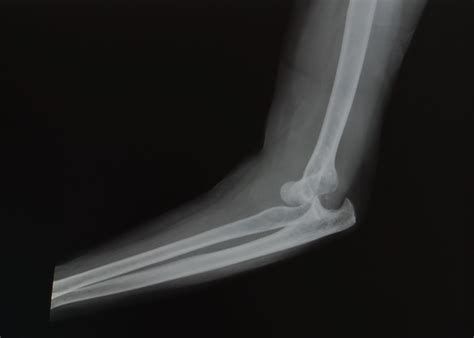

A dislocated elbow happens when the bones that make up the elbow joint—the humerus, ulna, and radius—are forced out of their normal positions. This can occur due to a fall, a direct blow to the elbow, or a sudden twisting motion. The most common type of elbow dislocation is when the ulna and radius are pushed out of alignment with the humerus.

• Imaging Tests: X-rays or other imaging tests may be ordered to assess the extent of the injury and check for any associated fractures.